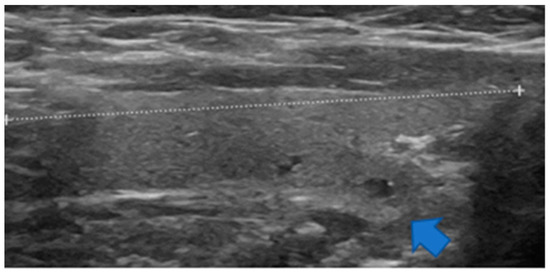

Figure 3.

Sagittal view of a non-enlarged thyroid lobe. At the lower portion, there is a downward and backward protrusion named the posteroinferior horn herein (blue arrow).